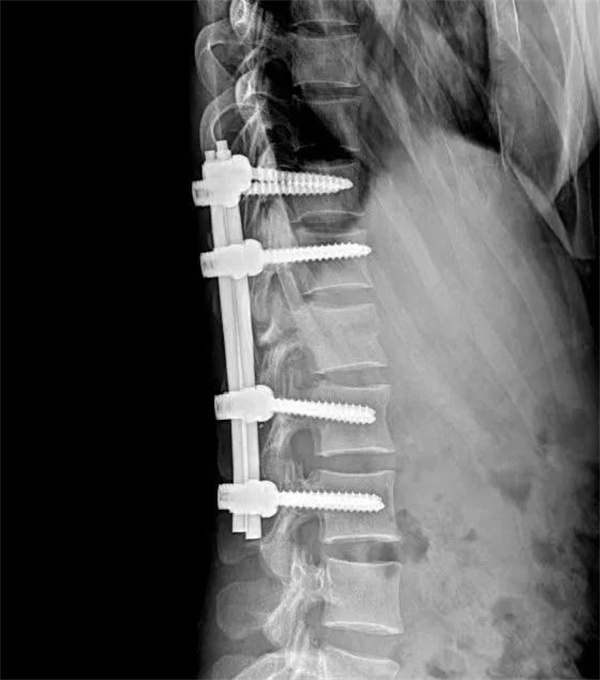

手术当日,在麻醉科的全力支持下,以主任医师饶放萍为主的骨一科医师团队凭借精湛的技术和丰富的经验,熟练地运用 Wiltse 肌间隙入路技术,巧妙避开重要神经、血管组织,精准地置入钉棒进行复位内固定。在团队的紧密协作下,术中出血仅 30ml,极大减少了患者的创伤应激反应,为术后快速康复奠定了坚实基础。

术前

术后